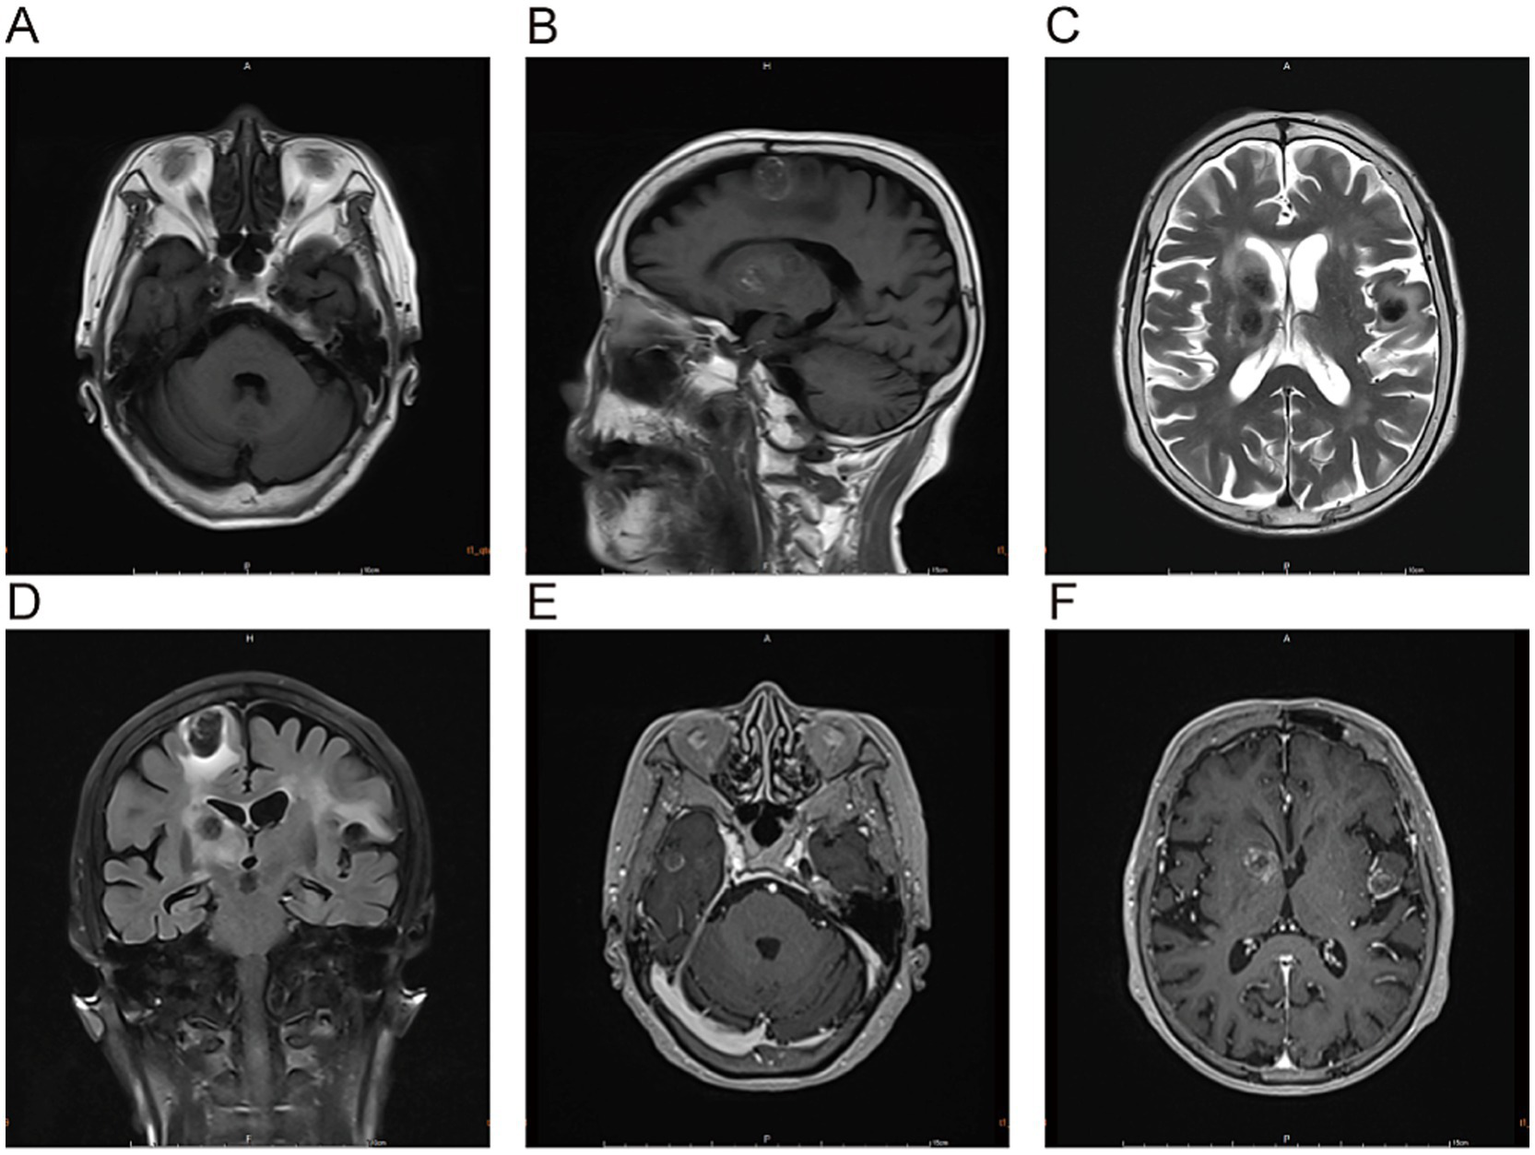

Admission Physical Examination: BP: 152/69 mmHg. No palpable enlarged superficial lymph nodes throughout the body. She was alert and oriented. Bilateral limb muscle strength was grade V. Muscle tone was normal. Physiological reflexes were present. Pathological signs were negative. Laboratory Tests: Prothrombin time (PT) 12.3 s, Activated partial thromboplastin time (APTT) 34.8 s, International Normalized Ratio (INR) 1.04, Platelet count 205 × 109/L—all of which were within normal limits. Serum creatinine 88 μmol/L, estimated glomerular filtration rate (eGFR) 59 mL/min/1.73 m2; serum albumin 3.62 g/dL (normal range: 4.00–5.50 g/dL); non-small cell lung cancer (NSCLC)-associated antigen CYFRA 21-1: 5.23 ng/mL (normal range: 0–3.3 ng/mL); pro-gastrin-releasing peptide (ProGRP): 118.00 pg./mL (normal range: 0–63 pg./mL); all other tumor markers were within normal limits. On March 10, 2025, cranial magnetic resonance imaging (MRI) with contrast (Figure 2) revealed multiple nodular mixed signal lesions in the right frontal-temporal lobe and basal ganglia, as well as the left frontal lobe, surrounded by patchy edema. Ring enhancement was observed on contrast-enhanced scans. Based on these findings, the preliminary diagnosis was “Possible brain metastases with hemorrhage.” Since our institution does not routinely perform diffusion-weighted imaging (DWI) and susceptibility-weighted imaging (SWI) sequences in clinical practice, this MRI examination was conducted using only T1-weighted, T2-weighted, fluid-attenuated inversion recovery (FLAIR), and contrast-enhanced sequences. Chest and abdominal computed tomography (CT) revealed bilateral multiple tiny pulmonary nodules and focal thickening of the gastric wall. After consultation with the Department of Respiratory Medicine, clinicians deemed these tiny pulmonary nodules benign proliferative nodules, with a recommendation for annual routine follow-up. No atypical cells were identified on gastroscopic pathological examination. On the patient’s second admission on March 14, 2025, electrocardiography (ECG) indicated a sinus rhythm (Figure 1B). A follow-up brain MRI scan performed on March 18, 2025, showed no significant changes in the size, signal intensity, or enhancement pattern of the lesions. Repeat brain MRI (Figure 3) and CT (Figures 4A–C) on March 30, 2025, demonstrated a reduction in the size of the lesions compared with prior images, with resolution of the surrounding edema. A further follow-up brain MRI on October 6, 2025 (Figures 4D–F) showed that most lesions had significantly decreased in size, and some had completely resolved.

Figure 2

The lesions in the right frontal-temporal lobe and basal ganglia region, as well as the left frontal lobe, predominantly exhibit high signal intensity on T1-weighted images (A,B) and low signal intensity on T2-weighted images (C). T2-FLAIRE sequences (D) reveal patchy perilesional edema surrounding the lesions. Contrast-enhanced scans (E,F) demonstrate ring enhancement.